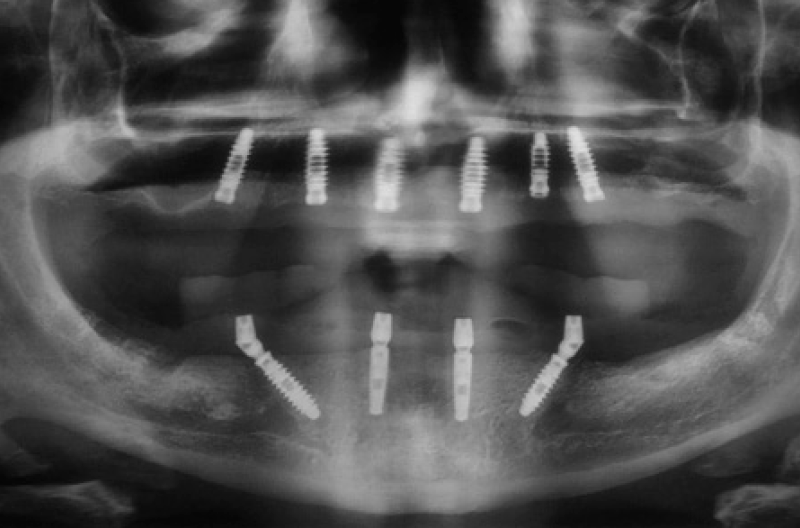

Fig. 26 – OPT a 4 mesi dallŌĆÖintervento

Fig. 60 – OPT post consegna. Le cappette Fixed in PEEK sono radiotrasparenti